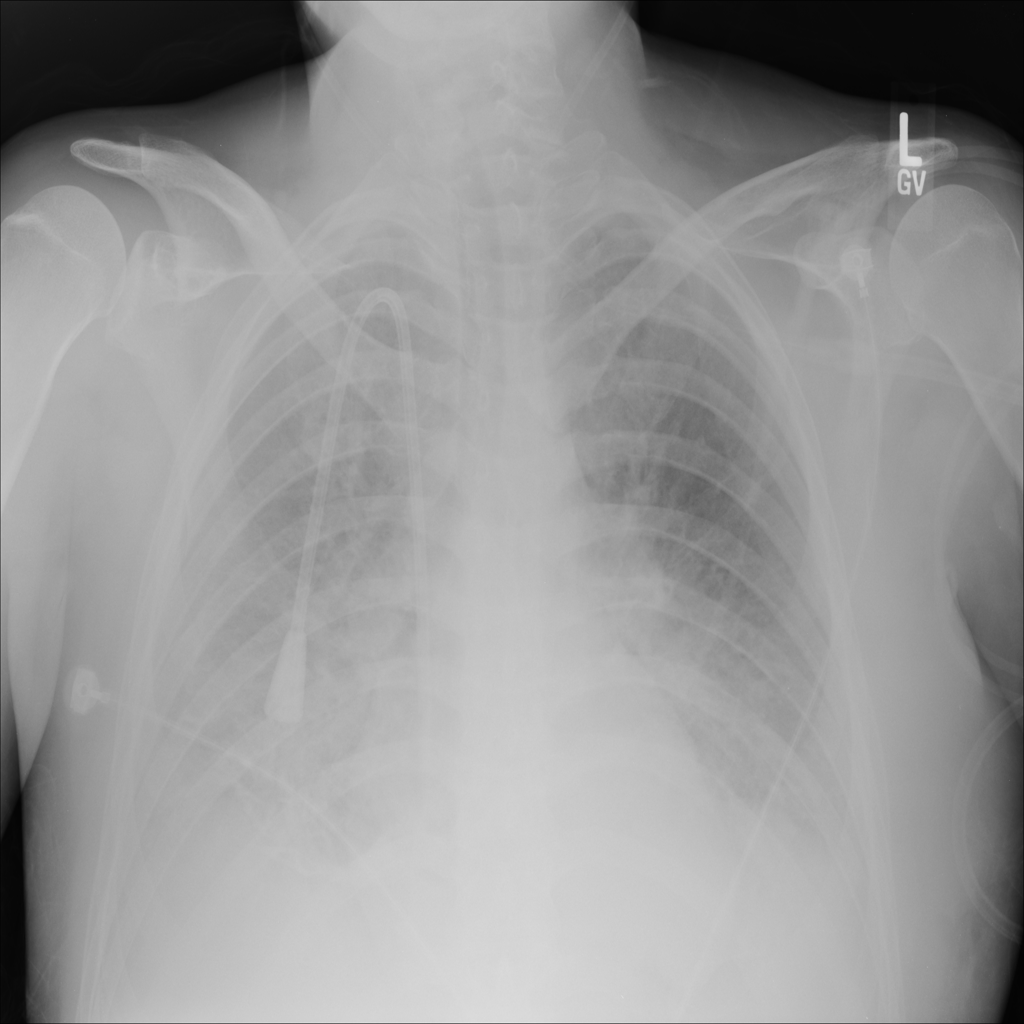

PAT-5B86 · IMG-009Edema

PAT-5B86 · IMG-009

PA